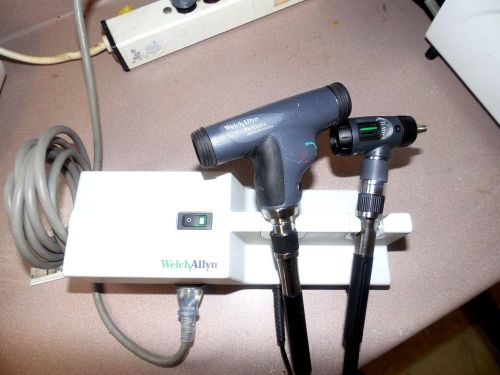

US $1,275.00

| Condition | Used

An item that has been used previously. The item may have some signs of cosmetic wear, but is fully operational and functions as intended. This item may be a floor model or store return that has been used. See the seller’s listing for full details and description of any imperfections.

| Seller Notes | “Please see test images.” |

Welch Allyn 767 Wall Transformer w/ Otoscope & Ophthalmoscope Heads 11710